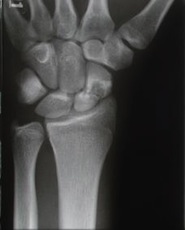

Röntgenbilder in normaler Aufnahmetechnik

Spezielle Röntgenaufnahme zur besseren Darstellung des Kahnbeins